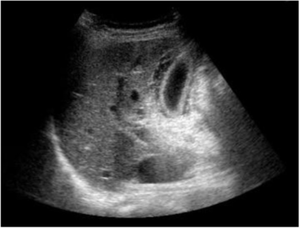

- Biliary ultrasound

- Gallstones

- Distinguish by characteristic "shadowing"

- GB wall thickening (>3mm)

- Pericholecystic fluid

- Sonographic Murphy's Sign (PPV 92%)